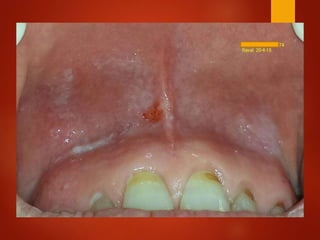

El documento es un registro médico odontológico que muestra las fechas de las visitas de un paciente al centro de salud El Raval, incluyendo exámenes y tratamientos realizados como la extracción de cálculos salivales en abril y mayo de 2012.